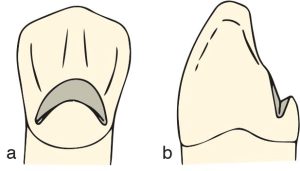

The “V” rest seat appears crescent-shaped when viewed from the lingual side, extending from one marginal ridge to the other, and is V-shaped when viewed from the proximal surface (Figure 10-44).

The diamond bur is held at a slight angle to the lingual surface, starting from one marginal ridge on the lingual side and progressing to the other marginal ridge; thus, a crescent shape is formed in the rest seat (Figure 10-45).

a) Preparation started with an inverted cone bur begins at one marginal ridge, passes over the cingulum, and ends at the other marginal ridge,

b) View from the proximal surface,

c)View from the lingual surface.